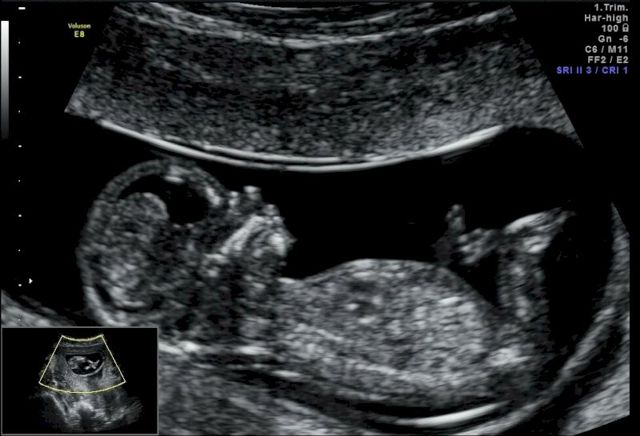

Мне было некого взять, все были против рождения ребенка. Получилось, что рожать мне вроде разрешили. Главврач психиатрической больницы сказал: «Ты, конечно, подумай, но, если ты захочешь рожать, тебе никто не запретит». Дважды уточнялся код моего заболевания, по этому коду следовало немедленное прерывание беременности. В моем случае, как только беременность устанавливается, лечение прерывается, можно только мёдик с молочком пить.